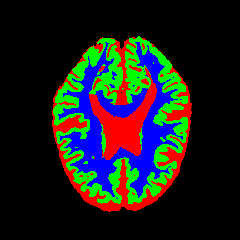

• OASIS-1 [34]: Derived from the Open Access Series of Imaging Studies, this dataset comprises T1-weighted MRI scans from 421 subjects (aged 18–96). The images were acquired with a resolution of 176×208176\times 208 pixels and a slice thickness of 1.25 mm (TR=9.79.7 ms, TE=4.04.0 ms, TI=2020 ms). Following standard protocols, we utilize the provided manual segmentation masks for Cerebrospinal Fluid (CSF), Grey Matter (GM), and White Matter (WM).

7 Qualitative Evaluation

Fig. 8 and Fig. 10 provide qualitative comparisons on the OASIS-1 and MRBrainS13 datasets, respectively. It is visually evident that the baseline predictions (c) and standard augmentations (e.g., (d), (g), (i)) frequently suffer from noisy artifacts, blurred boundaries, and mis-segmentation of intricate anatomical structures. In stark contrast, our ”Ours+” enhanced methods (e.g., (e), (h), (k)) consistently produce segmentation maps that are visibly cleaner, more spatially coherent, and demonstrate significantly sharper adherence to the Ground Truth (b). This superior fidelity is particularly noticeable in the complex sulcal patterns and holds true across all three backbones (rows), confirming that our framework yields more robust and anatomically plausible results.